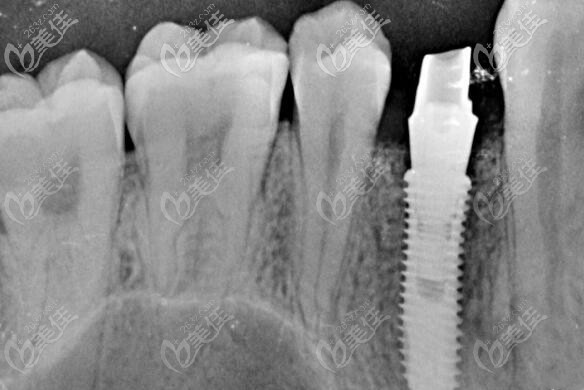

制定方案后,就幫顧客免費(fèi)拍了口腔CT全景片,從CT片中可以看出來有單顆缺失,但是牙槽骨條件良好,無炎癥,做種植也比較簡單,性價(jià)比比較高的韓國登騰種植體就可以做。

天津雅爾美口腔的醫(yī)生就利用數(shù)字化電腦進(jìn)行了簡單的設(shè)計(jì),避開血管神經(jīng),確種植體的位置,以及種牙后的牢固性。確方案后就開始手術(shù)。